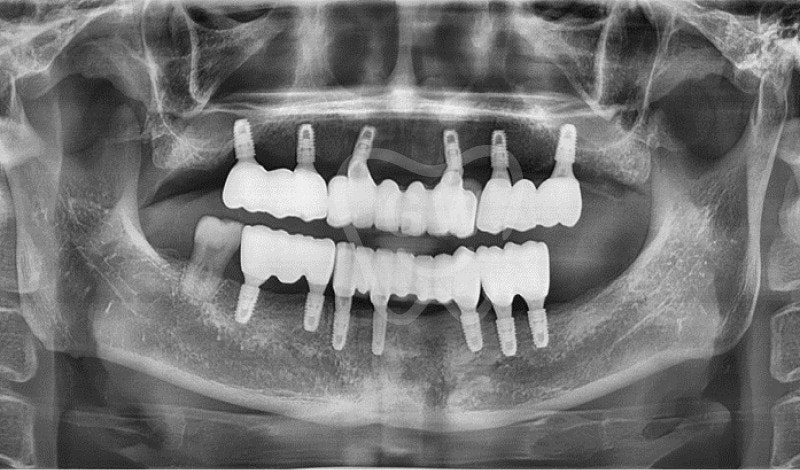

Mi abuelo dice que esta vez necesita implantes dentales en toda la boca.

Me preguntaba qué eran los implantes dentales completos, y oí que significa reemplazar una gran cantidad de dientes con implantes.

Sin embargo, optaron por implantes de boca completa y decidieron seguir adelante con ese tratamiento en esta ocasión.